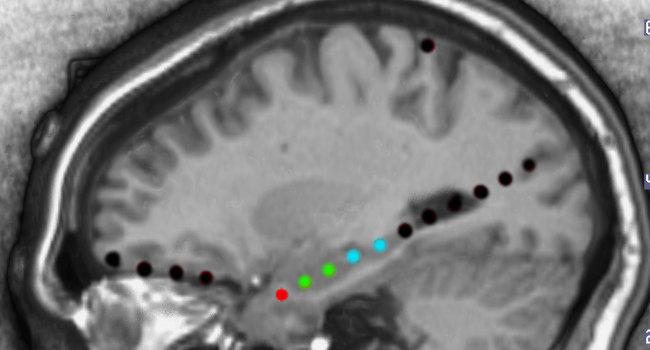

The ECoG lab is one of the only research labs in New England pushing the boundaries of knowledge and discovery in epilepsy research. We collect and focus on electrical data from patient’s brains to not only understand the effects of epilepsy on cognition, but also identify key findings in memory and attention. In addition, we explore various brain neurostimulation techniques to determine its impact on epilepsy and cognition.